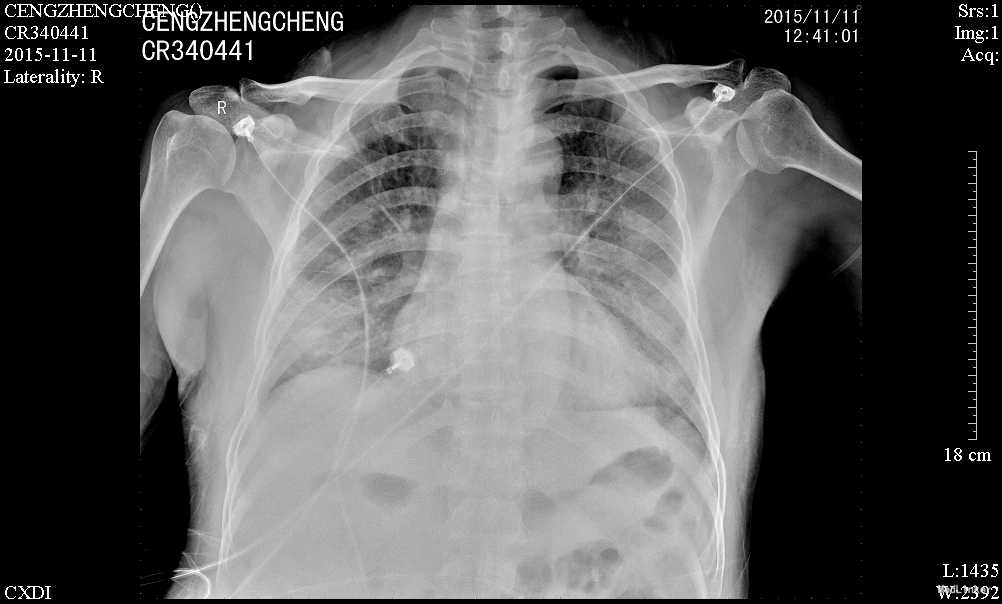

患者诉仍有咳嗽咳痰、呼吸困难、胸闷气促,咳白色粘痰,平卧及活动时加重,坐起后缓解,无发热,无咯血,精神、睡眠一般,饮食欠佳,大小便正常。高流量吸氧(7L/min)下血氧饱和度维持在93-95%,心率65-75次/分。查体:神志清楚,查体合作,胸廓未见异常;双肺呼吸音粗,双侧肺可闻及少许细湿罗音,无胸膜摩擦音;心界不大,心律齐,各瓣膜听诊区未闻及病理性杂音;腹平坦,无压痛、反跳痛,肝脏肋下未触及。辅助检查:感染三项:降钙素原(ProCT)6.00ng/ml;淀粉样蛋白A(SAA)281.8mg/L;C反应蛋白(CRP)。真菌D-葡聚糖(1_2_3βD)315pg/mL。巨细胞病毒定量(FQ_HCMV)2.85E+3copies/m。凝血功能:血浆D-二聚体测定(D-Dimer)0.85mg/L FEU;活化部分凝血活酶时间(APTT)46.8秒;血浆凝血酶原时间测定(PT)14.0秒。肾功能:尿素(BUN)19.52mmol/L;肌酐(CR)223μmol/L。肝功能:丙氨酸氨基转移酶(ALT)79U/L;天门冬氨酸氨基转移酶(AST)60U/L;总蛋白(TP)54.3g/L;白蛋白(ALB)21.8g/L150.67mg/L。前-脑利尿肽(Pro-BNP)572.1pg/mL。胸片示:1、两肺炎症,较前进展,建议治疗后复查;2、主动脉硬化;3、左肾区致密影,请结合临床其他检查;4、右第4肋骨陈旧骨折。

治疗:予更昔洛韦抗病毒、百炎净+亚胺培南西司他丁+莫西沙星抗细菌、免疫球蛋白冲击等抗感染治疗,注意根据患者肌酐清除率计算药物剂量,定期监测感染指标,调整抗感染方案;2、患者免疫抑制过程中出现感染,需降低免疫抑制强度,予甲强龙(80mg 1/日)、普乐可复(1.5mg 1/早,1.0mg 1/晚)、米芙(180mg 2/日)、五酯胶囊抑制免疫力;3、患者白蛋白较低,注意补充;4、注意护肝、降糖、碱化尿液等对症处理。2日后呼吸困难没有改善,查D葡聚糖315pg/mL,不排除真菌感染,加用科赛斯抗真菌治疗,持续20天后患者呼吸困难好转,血常规及CRP等值恢复正常

肾移植术后肺 部感染多发生在术后的早期,多数是在术后2~4月期间感染的。与这期间免疫抑制剂用量大,机体抵抗力低下有关。新型免疫抑制剂的临床应用,提高了肾移植的成功率,但也导致了机体免疫力降低,增加了各种感染的机会,以肺部感染最为常见,已成为肾移植患者死亡的主要原因。早期诊断和治疗对其预后尤为重要。 肾移植术后肺部感染早期的临床表现往往不典型,发热是其最常见、最主要的早期症状有发热,占 90%;许多患者入院时只有发热,开始为低热,咳嗽、咯痰、双 肺罗音均不明显,随后3-5天体温可达38.5℃以上;X线胸片已经显示肺部有点、片状阴影;病情发展迅速,咳嗽、咯痰及肺部罗音出现,患者很快会出现胸闷、呼吸困难、血氧饱和度下降,血气分析可有不同程度的低氧血症。所以肾移植术后早期出现发热,一定要摄胸片(或反复摄胸片),查白细胞计数,必要时行纤维支气管镜检查,或按肺部感染处理(排除排异反应)。 病原体的检测至关重要,需要反复、多次查血和痰的细菌、霉菌培养、痰涂片,必要时可行纤维支气管镜取分泌物查找病原菌。肾移植术后病毒感染较常见,特别是巨细胞病毒(CMV)最常见;由于CMV在正常人群中广泛存在,但多无临床症状,在免疫力低下时可使潜在的病毒复活、复制,导致肺部感染,死亡率高。激素对潜在的CMV复活影响很小,免疫抑制剂(如CSA、FK506等)可加速CMV的复制;CMV肺部感染无特异性,表现为高热、干咳、呼吸急促、白细胞减少,胸片多以片状或散在点片状影为主,也可扩散至全肺,呈间质性肺炎的表现;虽然获得CMV感染的直接证据很难,但PCR-CMV -DNA和CMV-IgM的检测可作为诊断依据。更昔洛韦对CMV感染治疗效果较好。 肾移植患者由于长期大量的用免疫抑制剂、肾上腺皮质激素,使机体抵抗力下降,加之强效广谱抗生素的应用,易造成机体菌群失调,导致二重感染,使机体正常分布的真菌大量繁殖、扩散。可适当抢先治疗,本例用卡泊芬净取得较好效果。肾移植术后肺部感染患者病情进展迅速,伴随着高热,可出现胸闷、呼吸困难、血氧饱和度下降等;治疗上除抗感染、化痰止咳外,必要 用呼吸机辅助呼吸,改善肺通气功能,提高血氧分压;可先采用无创的面罩吸氧,如氧合不满意,则改用有创的气管插管辅助通气,本例患者用无创呼吸机辅助通气取得较好效果。